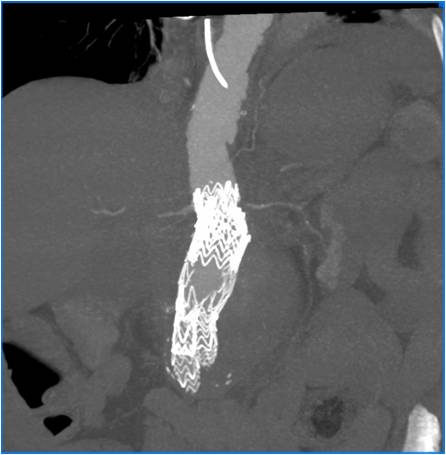

As seen from the presented table, eliminating type I EL required individual approach in all cases. Only in 4 cases the implantation of aortic cuff was performed in the isolated form to eliminate EL (Figure 1). In these cases, the aortic cuff was additionally fixed with Aptus EndoAnchors (Figure 2). In all cases, the procedure for EL elimination was confirmed with the intraoperative angiography, as well as by CT angiography or duplex ultrasonography with contrast enhancement after the surgery. No fatal outcomes were recorded.

Fig. 2. Intraoperative photo after implantation of the aortic cuff with fixation with Aptus EndoAnchors in Ia type endoleak.